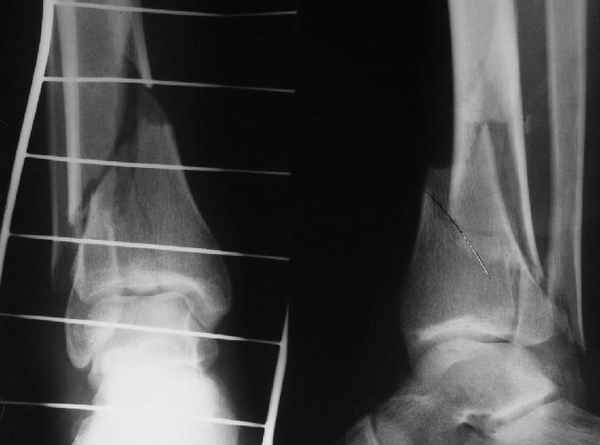

Да и нет! Зависит от перелома и способа остеосинтеза. А результат? (01)

Кликните для загрузки файла 01.jpg

Мы же говорили о проксимальном плече. При переломе tibia, конечно, речи о двух Y-спицах нет. Еще раз о них - пружинящая подвижность без "срезающих" перемещений фрагментов - дополнительный стимул к образованию периостальной мозоли.

А в данном случае - у нас был бы применен locked nail с еще меньшими дырочками на коже и с возможностью полной нагрузки немедленно после операции. Какие тут аргументы в пользу выбора пластины, а не интрамедуллярного гвоздя?